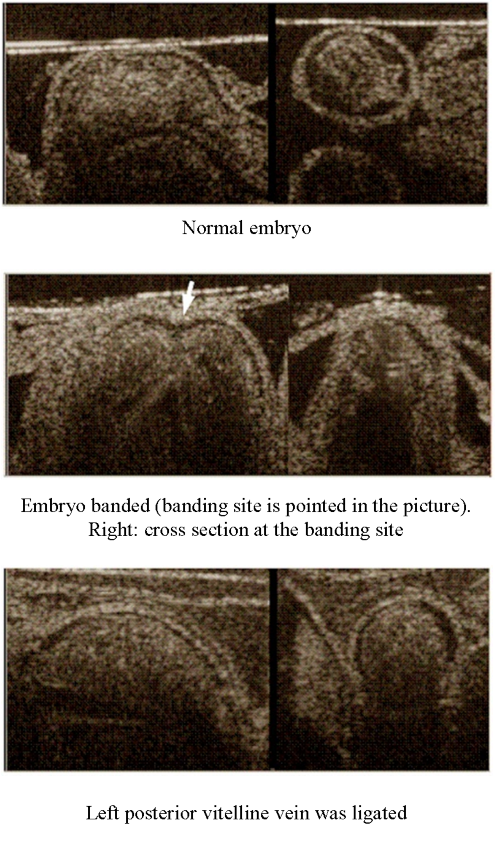

In vivo 3D imaging of Chicken Embryo

Image on the left in frame: longitudinal cut, Image on the right in frame: cross-sectional cut